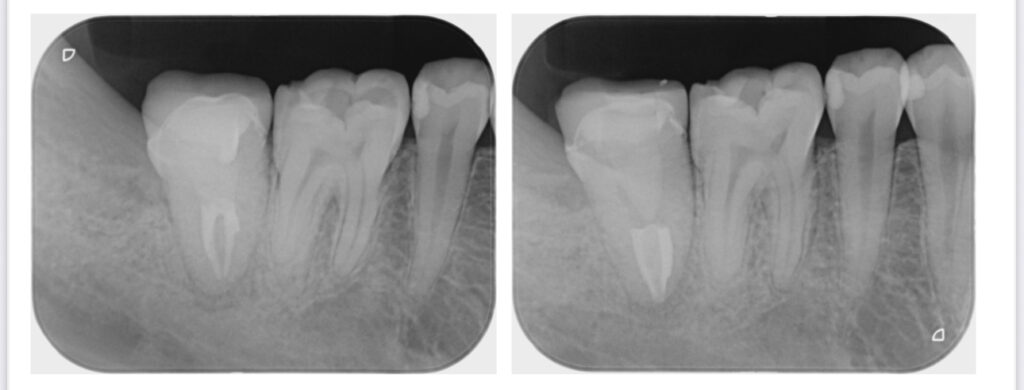

根管治療前後

根尖まで治療が完了していることが分かります。